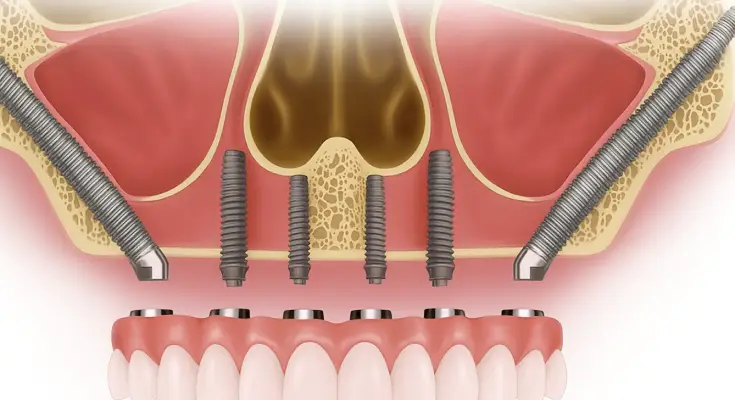

What are Zygomatic Dental Implants?

Zygomatic Dental Implants are viewed as another option to traditional implants. Traditional dental implants are placed in the jaw structures, but Zygomatic implants are placed in the cheekbones. These implants are angled into the zygoma bone before placement, offering a longer implant.

Giving teeth solid support allows people to live and conduct normal activities like before. Opting for the zygomatic route allows dental experts to use the cheekbone for implants. These structures offer greater bone mass and a solid structure for full arch restoration.